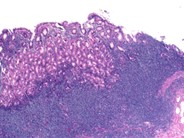

Gastric MALT Lymphoma - 2.

Category: Lymphoma: Mature B-cell and Plasma cell Neoplasms > Low-grade B-cell lymphoma > Extranodal Marginal Zone Lymphoma of the mucosa-associated lymphoid tissue (MALT lymphoma)

Marginal zone cells infiltrate lamina propria and muscularis mucosa.